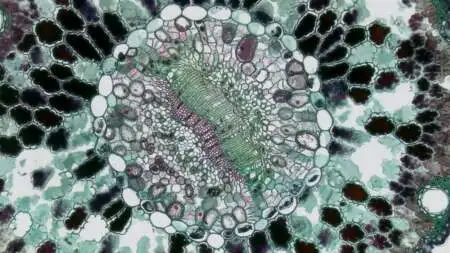

Ψηφιακή ακτινογραφία (χαρακτηριστική εικόνα σαν φύλλα κρεμμυδιού από την αντίδραση του περιοστέου και λυτική βλάβη στο οστό).

Βιοψία με βελόνη για την επιβεβαίωση της διάγνωσης και την έναρξη της θεραπείας. Χωρίς αποτέλεσμα βιοψίας δεν πρέπει να ξεκινάει η θεραπεία. Συνιστάται η βιοψία με βελόνη καθοδηγούμενη από αξονικό τομογράφο και να αποφεύγονται οι ανοικτές βιοψίες.